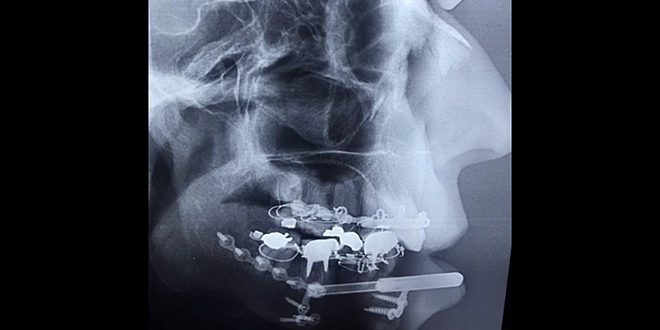

Damascus,(ST)- Dr. Khaled Auf, a specialist in Oral and Maxillofacial Surgery, reconstructed the entire lower jaw body of a 50-year-old woman who had lost it due to severe injury via a technique and device that he had previously invented and patented.

Dr. Aouf, head of the department of jaw surgery at the police hospital, explained to Sana that the technique is applied for the first time to build the entire mandible bone without the need for heterogeneous or self-implanting procedures, as it was previously applied partially, indicating that the woman was severely injured and the technology was ideal for her condition and proved successful in building the mandible between 20 Up to 25 days.

Aouf stated that the device allowed the building of the lower jaw bone and its completely loose soft tissue without the need to inoculate it with mucous membranes or bone grafts from as far away as the chest, foot and others, indicating that its removal takes place after bone calcification and mineralization and the idea of self-building of the bone in the new device is similar to the technique of managing fractures, which is the mode Two adjacent bone surfaces. The cells depicted in the blood develop within the contact area between them and bone-building cells that help build bone loss.